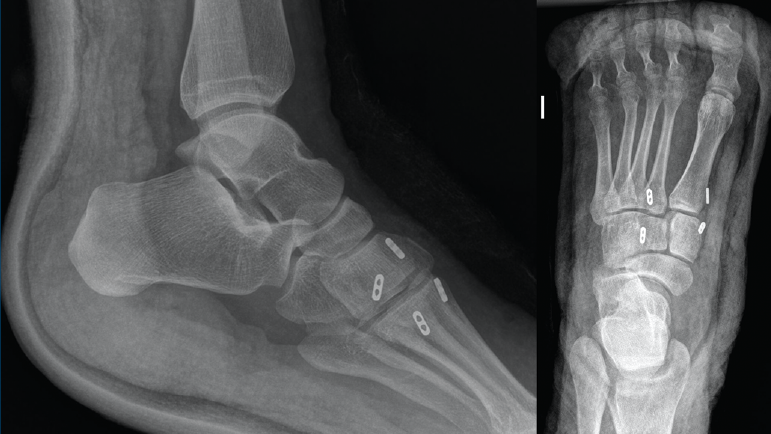

La revisión a los 3 meses mostró resultados satisfactorios en ambos casos, con tolerancia de la carga completa. Además, las imágenes radiológicas demostraron el mantenimiento de la reducción conseguida en el quirófano, sin movilización del material (Figuras 5 y 6).

Figura 5. Resultados radiográficos posquirúrgicos en el caso 1.

En el primer caso, la incorporación laboral fue a los 4 meses y, en el segundo caso, a los 6 meses; los pacientes no presentaron dolor. A los 10 meses postoperatorios el examen clínico no reveló evidencia de dolor en la zona quirúrgica y los pacientes habían reanudado todas sus actividades regulares, incluida la práctica deportiva, sin complicaciones. Además, las radiografías en ese momento revelaron una reducción anatómica de la lesión.

Figura 6. Resultados radiográficos posquirúrgicos en el caso 2.